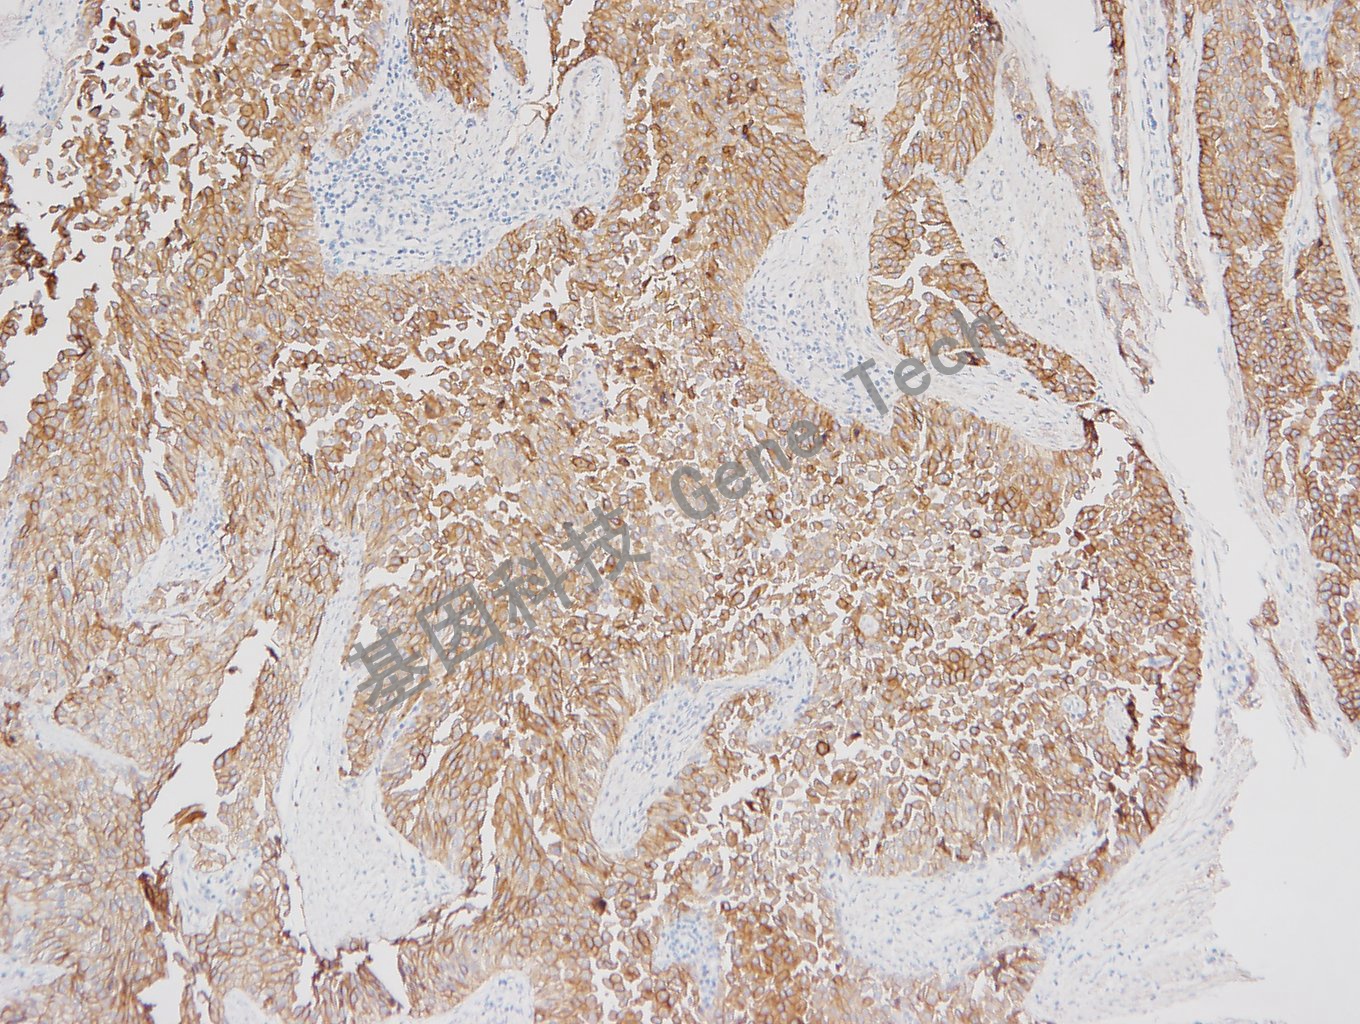

| 膀胱癌石蠟切片,用 Uroplakin Ⅲ(GT2173)染色,細(xì)胞膜/細(xì)胞漿陽性,DAB 顯色 | ||

| 預(yù)處理:高pH熱修復(fù) | 陽性部位:細(xì)胞膜/細(xì)胞漿 | 陽性對照:尿路上皮癌 |